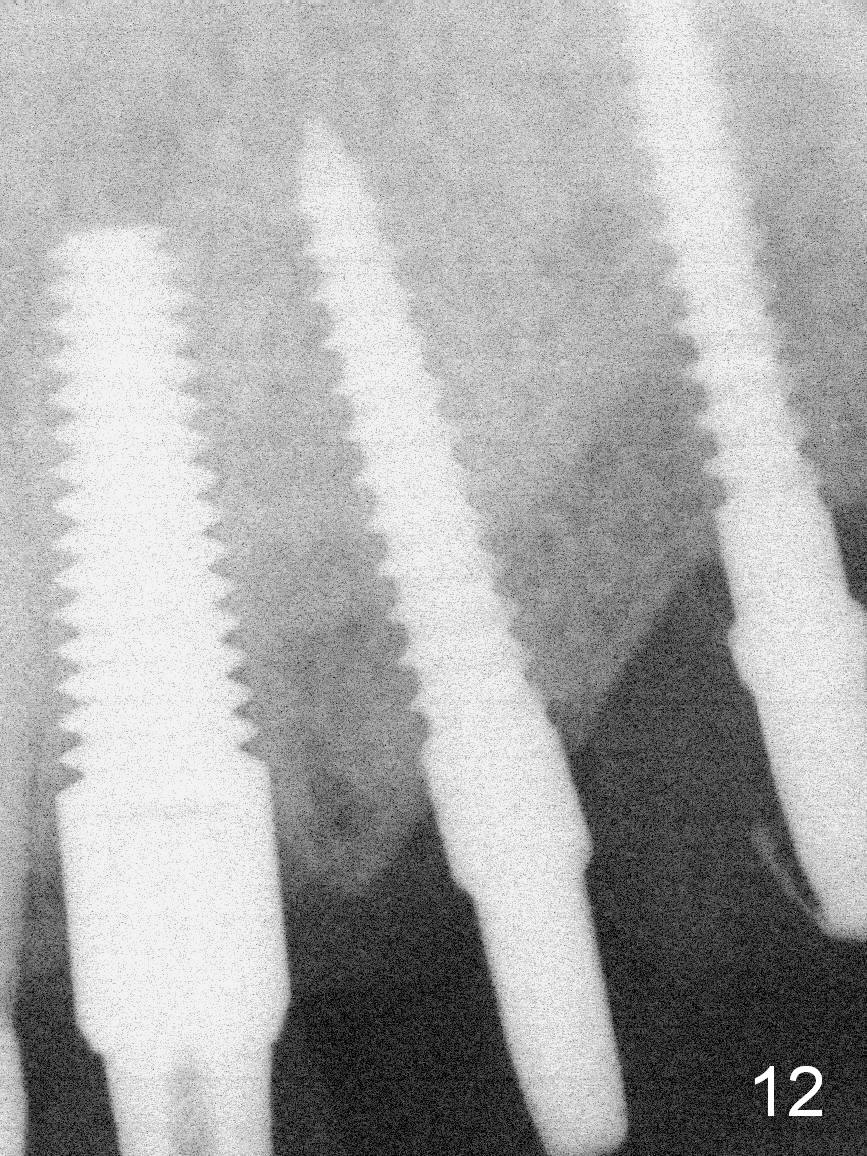

The patient returns for final restoration 3.5 months postop; it appears that the implants have osteointegrated (Fig.12,13). After reprep, there is no gross buccal plate atrophy at #10 (Fig.14).